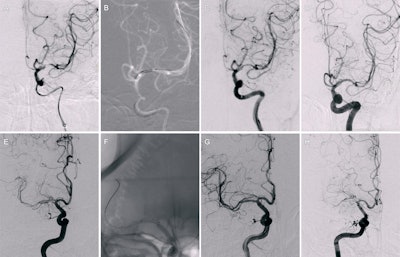

Example angiographic images from drug-coated balloon (DCB) angioplasty and bare-metal stent (BMS) placement procedures. (A-D) Images in a 49-year-old female participant who underwent DCB (2 × 9 mm) angioplasty for severe stenosis in the M1 segment of the left middle cerebral artery. Images (A) before and (B) during the procedure are shown. (C) Image immediately after the procedure shows improvement of the stenosis. (D) Image at 6-month follow-up examination reveals no restenosis. (E-H) Images in a 55-year-old male participant who underwent BMS (2.5 × 9 mm) placement for severe stenosis in the M1 segment of the right middle cerebral artery. Images (E) before and (F) during the procedure are shown. (G) Image immediately after the procedure demonstrates significant improvement of the stenosis, but (H) image at 6-month follow-up examination shows the development of restenosis and occlusion.RSNA

“In individuals with symptomatic ICAD with high-grade stenosis, DCB angioplasty reduced the six-month risks of angiographic restenosis and symptomatic restenosis and 30-day to one-year recurrent ischemic event rate compared with BMS placement,” Guan and colleagues wrote.